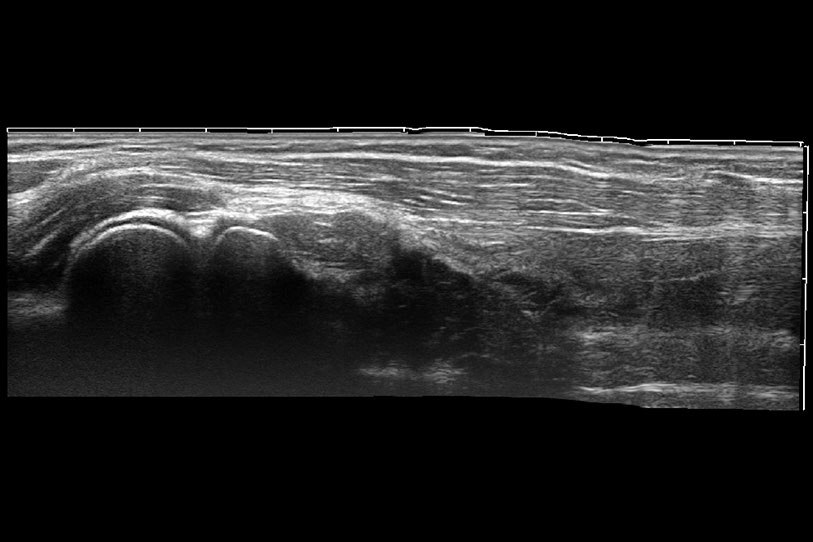

增强穿刺针在动物解剖结构中的位置,提高穿刺介入的安全性和准确性。